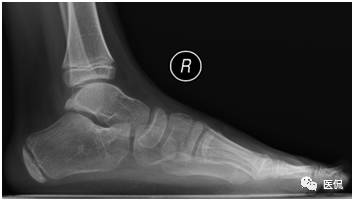

主诉 :主诉:双足内收、内翻畸形,呈马蹄状,且随年龄增长逐渐加重。

现病史:双足明显内翻、内收畸形,跟腱及跖筋膜挛缩、紧张,双足距骨、骰骨均脱位,骰骨外凸形成滑囊,双足跟内翻,尖小,双足背外侧着地负重,内踝深陷,背伸活动功能障碍,不能独立行走,双小腿肌肉萎缩。

足部非负重正位片:足前部明显内收,跖骨远端及趾骨平铺,跖骨近端聚拢、外移;第1跖骨萎缩,第5跖骨肥大,密度增高;距骨扁而宽,距骨中轴线明显远离第1跖骨,跟骨内翻呈马蹄状,跟骨中轴线明显远离第5跖骨,跟距关节半脱位;跗骨形态失常,舟骨外侧发育较小,相应部分与距骨形成关节中创网,但距舟关节半脱位,跗骨关节间隙变窄;胫骨远端骨化中心外侧部分较内侧部分明显扁小。

足部负重侧位片:跟骨马蹄位,其上下径增大;舟骨外侧发育较小,距舟关节半脱位;即使强迫前足向背弯曲,其较后足仍向足底弯曲(弓形足);跟距角变小(正常25-45度),严重时跟骨与距骨中轴线近似平行。